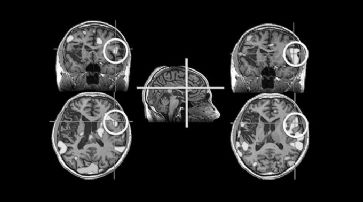

Chemikalie verhindert Absterben von Gehirnzellen

Leicester - Die Entdeckung der ersten Chemikalie, die das Absterben von Gehirngewebe bei neurodegenerativen Erkrankungen verhindern kann, gilt als historisches Ereignis in der medizinischen Forschung.

Weitere Tests sind jedoch für die Entwicklung von Medikamenten erforderlich, die von Patienten eingenommen werden können.

Ein mögliches Medikament könnte zur Behandlung von Alzheimer, Parkinson, der Huntington-Krankheit und anderen Erkrankungen eingesetzt werden. Erste Tests an der University of Leicester haben nachgewiesen, dass das Absterben von Zellen durch Prionenerkrankungen verhindert werden kann.

Das Team der Medical Research Council Toxicology Unit konzentrierte sich auf die natürlichen Abwehrmechanismen der Gehirnzellen. Übernimmt ein Virus eine Gehirnzelle, kommt es zu einer Ansammlung von viralen Proteinen. Die Zellen reagieren mit einer fast vollständigen Einstellung der Proteinproduktion. Sie versuchen damit, die Ausbreitung des Virus zu verhindern.

Eiweissproduktion entscheidend

Bei zahlreichen neurodegenerativen Erkrankungen kommt es zur Produktion von fehlerhaften oder falsch gefalteten Eiweissmolekülen. Dadurch werden die gleichen Abwehrmechanismen aktiviert. Sie haben jedoch schwerwiegendere Folgen. Die falsch gefalteten Proteine bleiben und die Gehirnzellen stellen die Eiweissproduktion so lange ein, bis sie irgendwann absterben.

Wiederholt sich dieser Vorgang in Neuronen im Gehirn, kann die Folge eine Zerstörung der Bewegungsfähigkeit, des Gedächtnisses oder gar der Tod sein. Die Wissenschaftler gehen davon aus, dass dieser Vorgang bei zahlreichen verschiedenen Arten der Neurodegeneration eintritt.

Das Absterben von Zellen kann durch Prionenerkrankungen verhindert werden.(Symbolbild) /

So könnte eine sichere Möglichkeit zur Unterbrechung des Mechanismus die Behandlung einer Vielzahl von Erkrankungen bedeuten.

Erste Tests mit Mäusen getätigt

Das Team um Giovanna Mallucci nutzte ein Gemisch, das verhindert, dass diese Abwehrmechanismen stattfinden und stoppte damit die Neurodegeneration. Die in Science Translational Medicine veröffentlichte Studie zeigt, dass Mäuse mit Prionenerkrankungen schwere Symptome entwickelten. Innerhalb von zwölf Wochen starben die Tiere.

Jene Mäuse, die mit dem neuen Wirkstoff behandelt wurden, wiesen jedoch keinen Abbau des Gehirngewebes auf. Laut Mallucci ist es den Tieren gut gegangen. "Wirklich aufregend ist, dass ein Wirkstoff die Neurodegeneration erstmals völlig verhindert hat. Dieser Wirkstoff kann noch nicht beim Menschen eingesetzt werden. Damit ist aber bewiesen, dass es möglich ist und das ist schon einmal ein Anfang." Die Forscher führen derzeit an Mäusen Tests für andere Formen von Neurodegeneration durch. Ergebnisse wurden noch nicht veröffentlicht.

Nebenwirkungen sind jedoch ein Thema. Der Wirkstoff hat Auswirkungen auf die Bauchspeicheldrüse. Das bedeutet, dass die behandelten Tiere an einer leichten Form von Diabetes erkrankten und an Gewicht verloren. Ein Medikament, das bei Patienten eingesetzt werden kann, dürfte daher nur im Gehirn wirken.